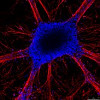

La ricerca, pubblicata sul Journal of Neuroscience, dice il comunicato, “fornisce una importante dimostrazione delle proprietà di alcune cellule staminali isolate dal tessuto nervoso umano ai primi stadi di sviluppo embrionale. I ricercatori hanno dimostrato infatti che cellule isolate da specifiche regioni del cervello, in particolare dal cervelletto, possono essere mantenute e moltiplicate in vitro per lungo tempo, senza perdere le caratteristiche originali.”

L’Università di Cambridge aveva infatti affidato ai ricercatori del Nico “il trapianto delle cellule staminali umane nel cervelletto di topi neonati: gli esperimenti, durati alcuni anni, hanno confermato che le cellule trapiantate sono capaci di differenziarsi in neuroni del cervelletto simili a quelli dell’ospite; l’isolamento di questa linea di cellule staminali offre un nuovo sistema sia per studiare i meccanismi di sviluppo nel cervelletto umano, sia per produrre tipi cellulari specifici, facilmente differenziabili e di cui si può controllare il differenziamento, e ampiamente stabili.”

“Rispetto ai trapianti di questo tipo fatti finora – spiega il prof. Ferdinando Rossi, direttore del Nico – le cellule così prodotte hanno il vantaggio di essere omogenee, e quindi a lungo termine utilizzabili efficacemente per la cura di patologie degenerative, come nel caso delle atassie spino-cerebellari: si tratta di un risultato molto significativo perchè dimostra che la ricerca sulle staminali, se condotta in modo serio, produce risultati certi e dimostrabili, anche se questo comporta anni di lavoro e di attesa; dimostra infine l’importanza di sostenere, anche a livello europeo, collaborazioni tra ricercatori con competenze ed esperienze complementari”.